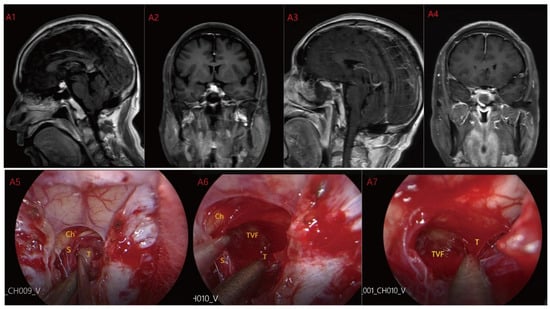

Figure 2.

Case 2: Type II: The tumor located on the suprasellar region and compressed or penetrated the third ventricle floor (TVF) (A1,A2). During EEA surgery, the complete pituitary stalk can be seen via TCPCA, and the tumor is located behind and above the pituitary stalk (A5,A6). The tumor adhered closely to the floor of the third ventricle, and part of it protruded into the third ventricle during the operation. The tumor achieved GTR (A7). Postoperative MRI were shown in (A3,A4). Optic chiasm (Ch), foramen of Monroe, massa intermedia (MI), cerebral aqueduct (CA), tumor (T), pituitary stalk (S).